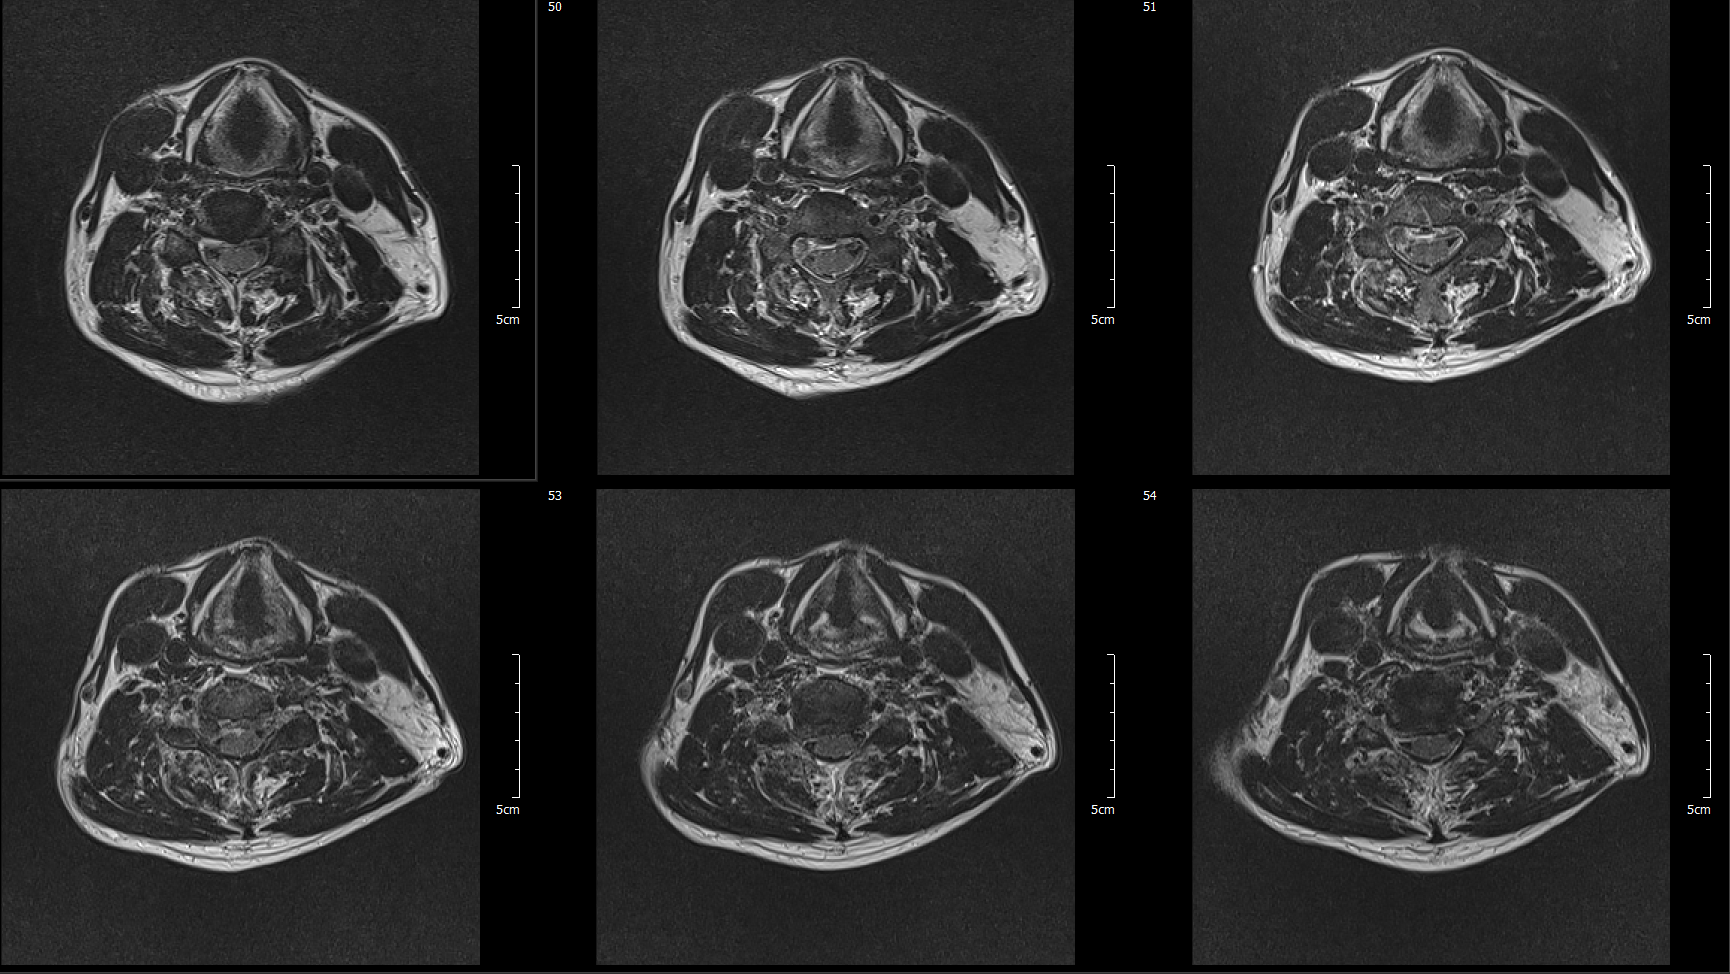

MRI

C5-6 : Ruptured HCD, Rt